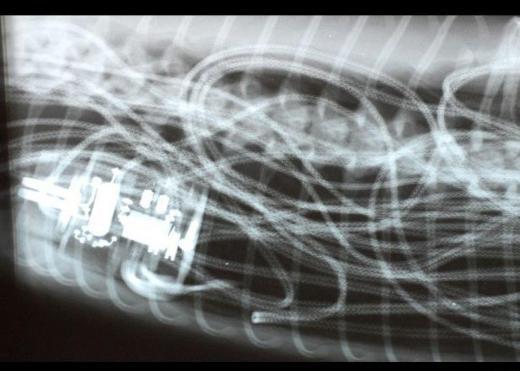

9. Üç buçuk metre uzunluğundaki bir piton yılanı olan Houdini, sahibi tarafından sıcak olsun diye kafesine konulan elektrikli battaniyeyi yutunca, battaniyenin içindeki tesisat içinde sıkışıp kaldı. Yılan, başarılı bir operasyonla eski haline geri döndü.

Üç buçuk metre uzunluğundaki bir piton yılanı olan Houdini, sahibi tarafından sıcak olsun diye kafesine konulan elektrikli battaniyeyi yutunca, battaniyenin içindeki tesisat içinde sıkışıp kaldı. Yılan, başarılı bir operasyonla eski haline geri döndü.